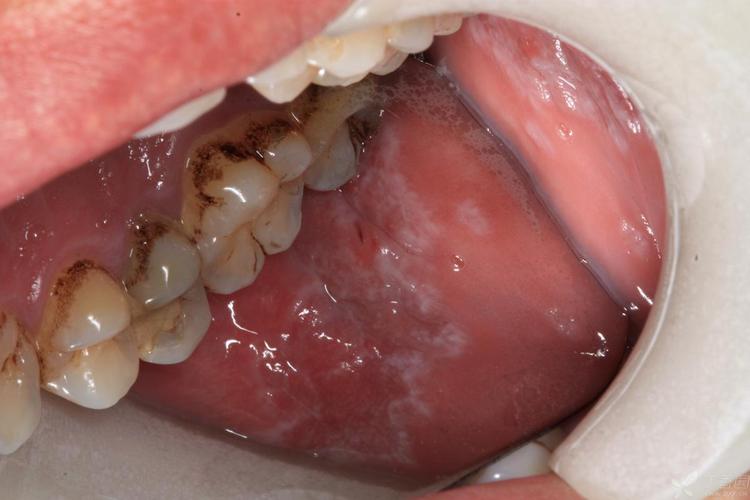

口腔扁平苔藓本身是一种良性的、慢性的炎症性疾病,它不会直接导致人死亡。

口腔扁平苔藓是一种常见的口腔黏膜疾病,可以理解为口腔黏膜的一种“慢性炎症”或“过敏反应”,它的病因目前尚不完全明确,但普遍认为与以下因素有关:

- 癌变风险极低: 这是最关键的一点,虽然极少数(约1%-2%)的长期糜烂型扁平苔藓有发生癌变(转化为鳞状细胞癌)的可能,但这个概率非常低,并且通过定期复查完全可以早期发现和处理,它和癌症之间划不了等号。